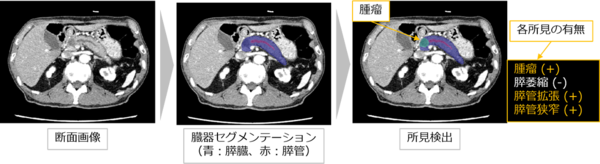

腫瘤(直接所見)が描出されていないが膵萎縮・膵管拡張・膵管狭窄(間接所見)を検出した症例(ステージ0)

富士フイルムと神戸大学は,CT画像から膵臓がんの早期発見を支援するAI技術の開発を目指し,2021年8月より,神戸大学大学院医学研究科の児玉 裕三教授・村上 卓道教授を中心としたチームのもとで共同研究を進めている。今回,膵臓がん患者を含む約1,000症例の造影CT画像をAIに学習させ,腹部の造影CT画像から膵臓がんが疑われる所見を検出する技術の開発に成功した。本技術は,膵臓がんの直接所見である腫瘤のみならず,間接所見である膵萎縮・膵管拡張・膵管狭窄などを検出する。本技術を活用して医師の負担を軽減することで,より精度の高い診断につながることが期待できる。